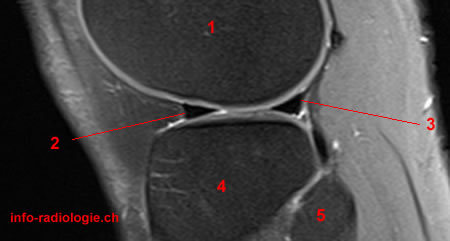

IRM du genou pour douleurs et hydarthrose récidivante: que voit-on?

Anse de seau du ménisque

Un patient s’est présenté aux urgence pour blocage aigu du genou, une IRM est réalisée que voit-on?

Anse de seau luxée dans l’échancrure intercondylienne

Un patient a une sensation d’instabilité avec dérobement du genou, avec douleur et hydarthrose récidivante

Voici une IRM des ménisques. Diagnostic?

IRM normale des ménisques